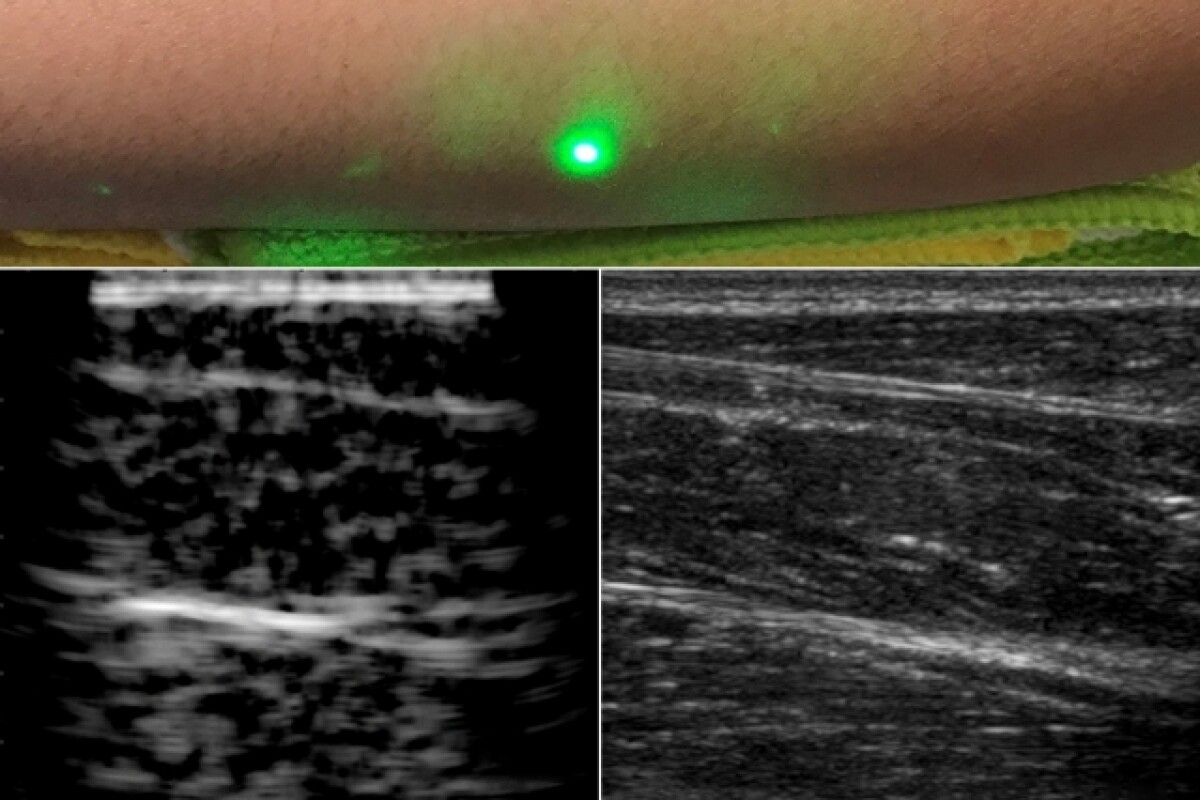

Effects can range from mild skin burns to irreversible injury to the skin and eye The biological damage caused by lasers is produced through thermal, acoustical and photochemical processes Thermal effects are caused by a rise in temperature following absorption of laser energy The severity of the damage is dependent upon several factors, including exposure duration, wavelength of the beam, energy of the beam, and the area and type of tissue exposed to the beam. An opposite effect was observed when subjects held their breath—the intensity of the laser radiation through tissues lowered It might be connected with the fact that while holding the breath,. Nausea, vomiting, diarrhea, or indigestion;.

Mit Reveals First Ever Laser Ultrasound Pictures Of A Human Body